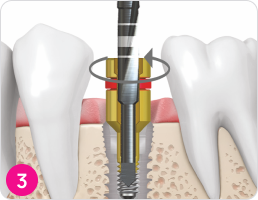

Направляющая для сверла с обратным вращением (реверсивного сверла)

Выберите подходящий размер направляющей для сверла с обратным вращением. Используя направляющую для инструментов, затяните направляющую для сверла к импланту по часовой стрелке до соприкосновения с винтом внутри импланта.

Сверло с обратным вращением (реверсивное сверло)

Выберите подходящий размер реверсивного сверла и соедините его с угловым наконечником. Введите реверсивное сверло в направляющую для реверсивного сверла, присоединенную к импланту. Против часовой стрелки на скорости 2000 об/мин углубитесь сверлом на 1-2мм в поверхность сломанного винта. Проверяйте маркировочную линию на сверле ( интервал маркировки 1 мм) и охлаждаете ирригацией на всем протяжении сверления.